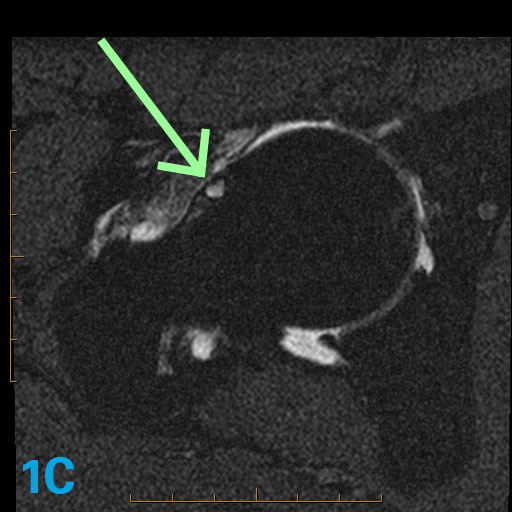

The three axial oblique images in this 43-year-old with hip pain demonstrate an abnormality. What are the associated potential imaging findings that might accompany this abnormality?

The lack of tapering of the femur head to the neck is known as asphericity. This lack of tapering is associated with a bump in the anterior aspect of the femoral head neck junction. The bump is also associated with a friction-related pseudocyst ("herniation pit") that occurs when the hip is in flexion and especially in flexion-internal rotation as this area rubs across the acetabulum. Sometimes the friction produces edema but not an actual cyst.

Clinically, such patients often experience pain in hip flexion worse in internal more than external rotation. This case illustrates an axial oblique head neck junction shape of Cam or Type 1 hip impingement syndrome. For more case review, check out MRI Online.